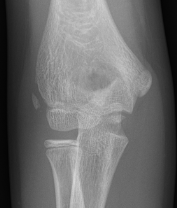

Age of appearance in girls CRITOE

| Center | Simple | Accurate |

| Capitellum | 1 | 1 |

| Radial head | 3 | 5 |

| Internal epicondyle | 5 | 7 |

| Trochlea | 7 |

10 |

| Olecranon | 9 | 10 |

| External epicondyle | 11 | 11 |

Boys on average 2 years later in every center except capitellum

1 year old male: C 5 year old female: CR

8 year old male: CRIT

11 year old male: CRITOE